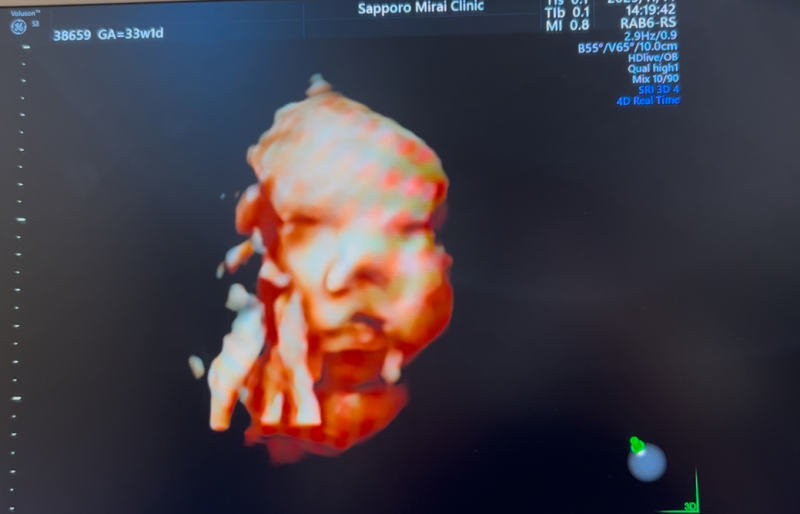

妊婦健診で4Dのエコー写真を撮って頂けるのですが、

顔の特徴がダウン症の特徴と同じのような感じがして

不安です。鼻は低いし目がつり目?のような浮腫んでるような…。

※写真は28週、35週、32週の順です。

実際にエコー写真でダウン症顔貌かの判断は、できないかなと思います。私からみて、エコーでみる赤ちゃんの顔としては、特徴的な顔貌の印象はないです。

エコー画像は、実際に見る感じとは、少し違う感じに見えるかなと思います。